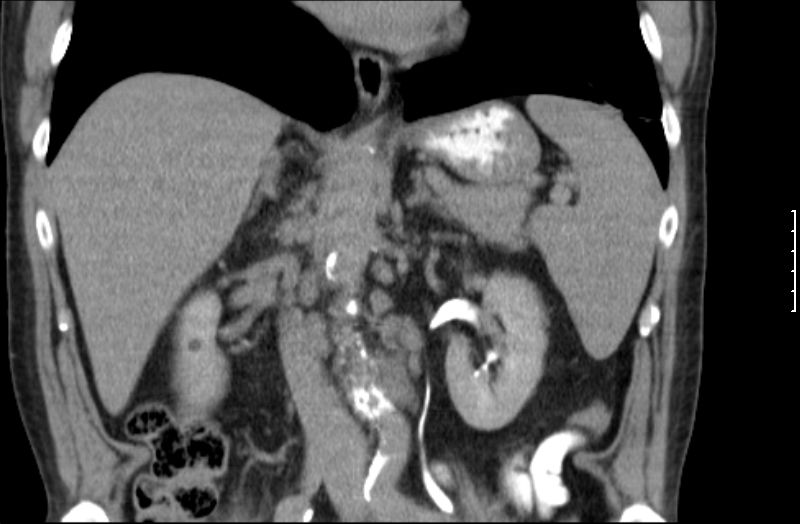

| Diagnostik | 68jähriger Mann mit B-Symptomatik und Splenomegalie.